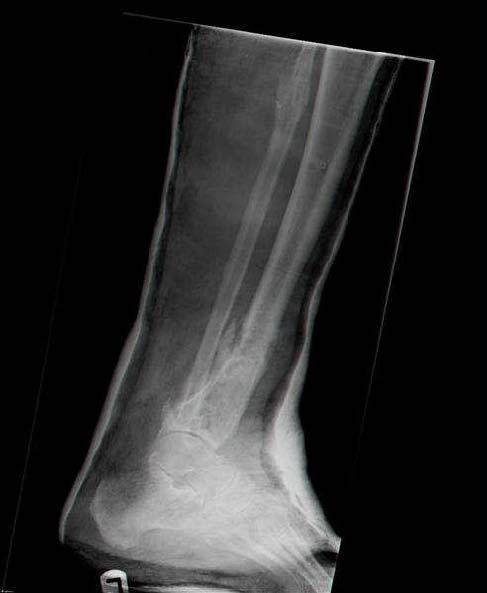

Sorry, I wiil tray now pictures of my case.